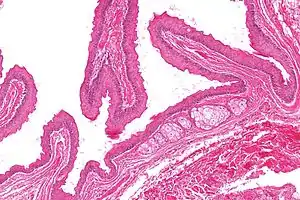

| Micrograph of a steatocystoma showing the characteristic corrugated eosinophilic lining. H&E stain | |